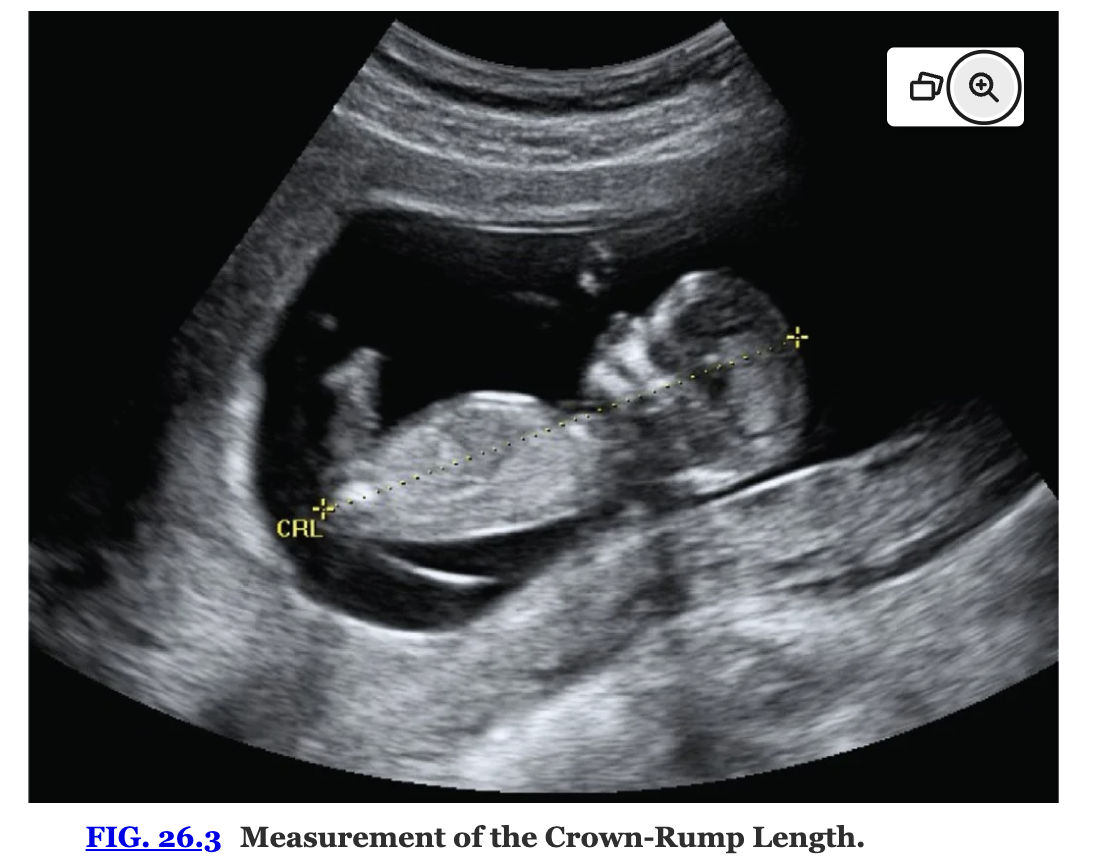

Either the maximum embryo length or the crown-rump length is used during the first trimester to measure the early embryo

After the first trimester, the biparietal diameter (BPD), head circumference, abdominal circumference, and femur length are measured instead.